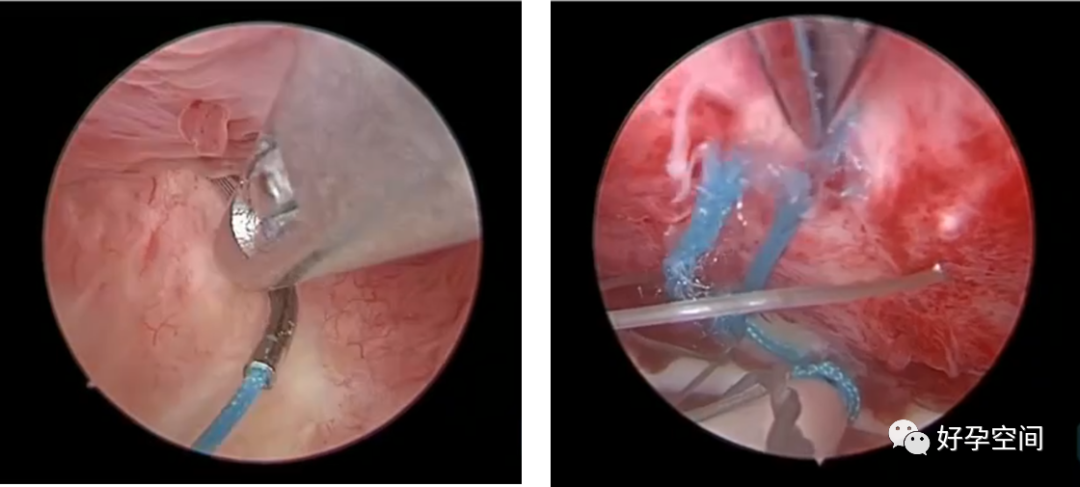

试管助孕前双侧输卵管积水,腹腔镜及开腹手术失败,宫腔镜电针电凝封堵输卵管开口

既往试管助孕前输卵管开口植入弹簧圈,再次移植前宫腔镜检查,弹簧圈包埋组织内,不见痕迹